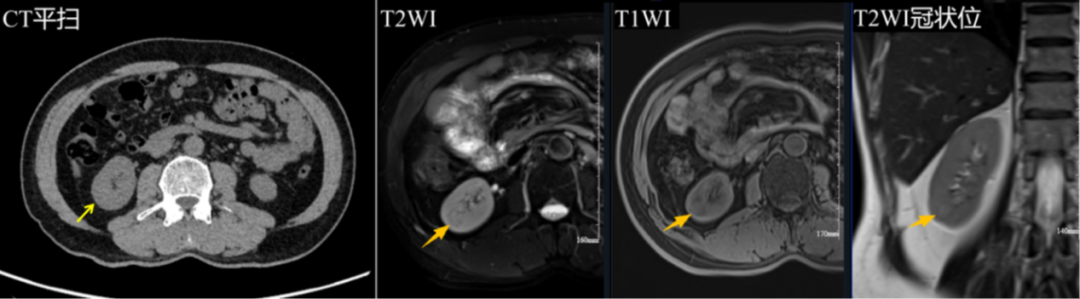

叶先生的 MR 平扫显示:右肾下极见一类圆形混杂信号结节,直径约 16 mm。虽然报告建议进一步检查,但危机的真正信号,被经验丰富的诊断医生第一时间捕捉。

价值: 清晰显示脏器结构,如叶先生肝内的囊肿和右肾下极的结节。

局限: 平扫影像主要提供形态和基础信号信息,对于结节的性质(良性或恶性)判断能力有限。 叶先生的肾结节虽被检出,但其良恶性悬而未决,若按常规流程等待,可能错失最佳干预时机。

影像中心的梁江涛主任在报告审核环节,凭借对影像细节的敏锐洞察,第一时间将此次影像与叶先生一年前(2024 年 11 月 8 日)的数据进行了比对。他发现这个右肾下极结节在一年内「较前略增大」。这一细微但关键的变化,结合结节在 DWI 序列呈「略高信号」等特征,高度提示其存在恶性病变风险。梁主任当即做出专业决策:建议立即加做肾脏增强 MRI 检查。